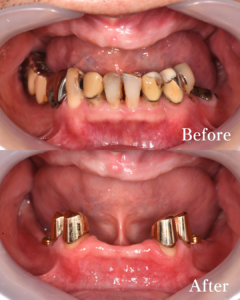

治療前後比較(正面)

上下ともに総入れ歯の安定が良くなり、しっかりと噛めるようになりました。また見た目も自然で、総入れ歯を使っているとは分からない綺麗な仕上がりになりました。

治療前後比較(下顎)

長期的に長持ちしない歯は、抜歯を行いましたが、それ以外のしっかりした歯はなるべく残して、総入れ歯の固定になるように配慮して治療を行なっております。